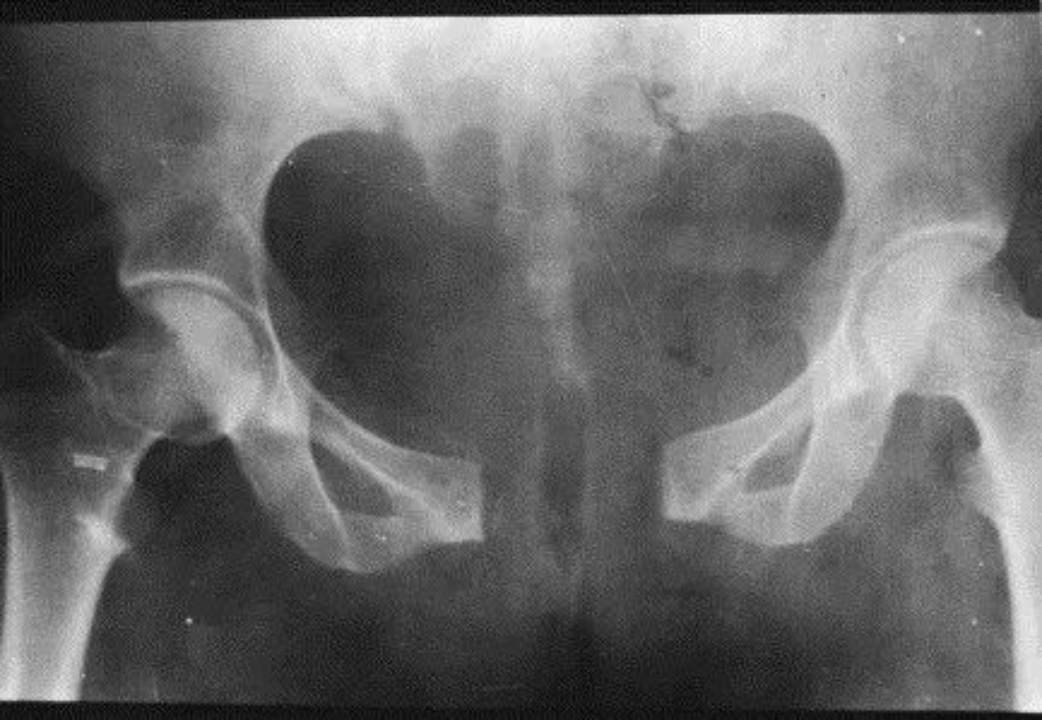

上图为产后耻骨联合分离的患者,不能坐、站,就是老百姓说的生娃生“瘫痪”了。